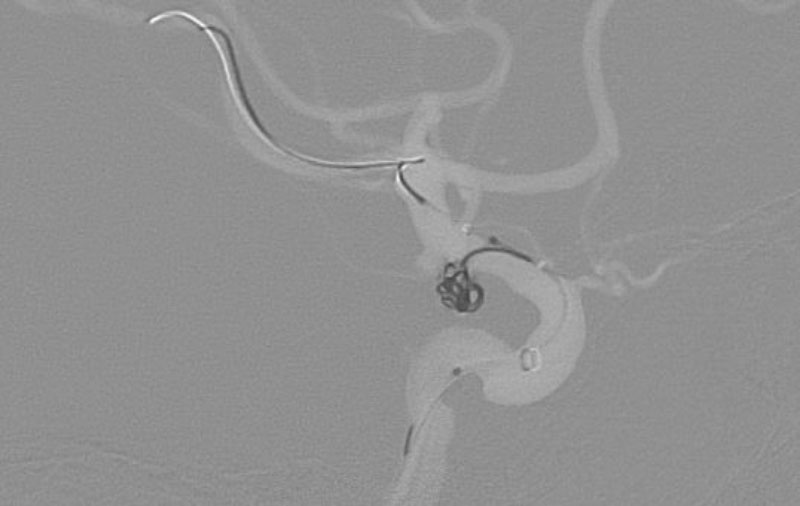

No.1628 手術後